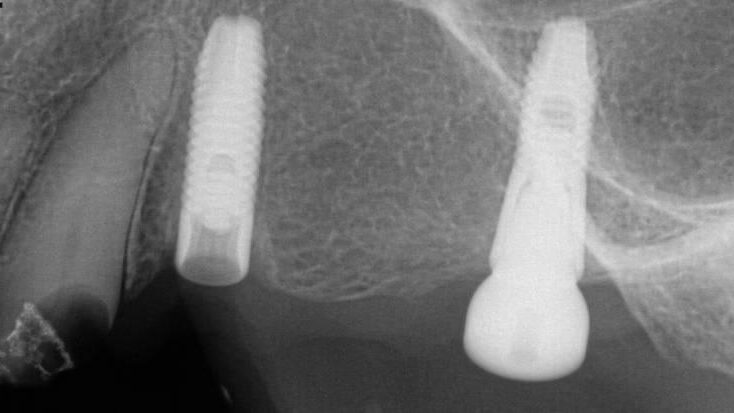

A Routine Type I Case Transformed Into a Type V or VI – 0044

This case showcases a Routine Type I Case Transformed Into a Type V or VI When Initial Recovery Efforts Failed.